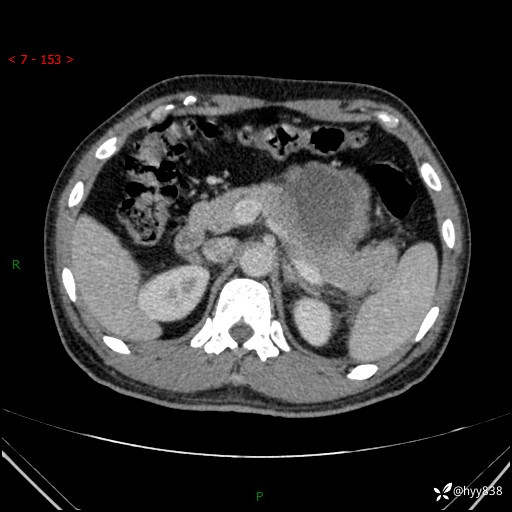

病例39岁/女,左侧腰痛入院。腹腔囊实性肿块,定位、定性---结果公布~

性别:男

年龄:39岁

简要病史:左侧腰痛待查,CT发现腹腔占位

腹部CT平扫+增强